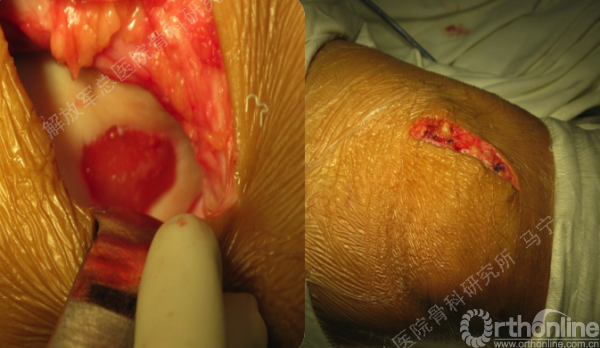

软骨缺损范围的测量。

复位后屈伸膝关节,观察补片情况。